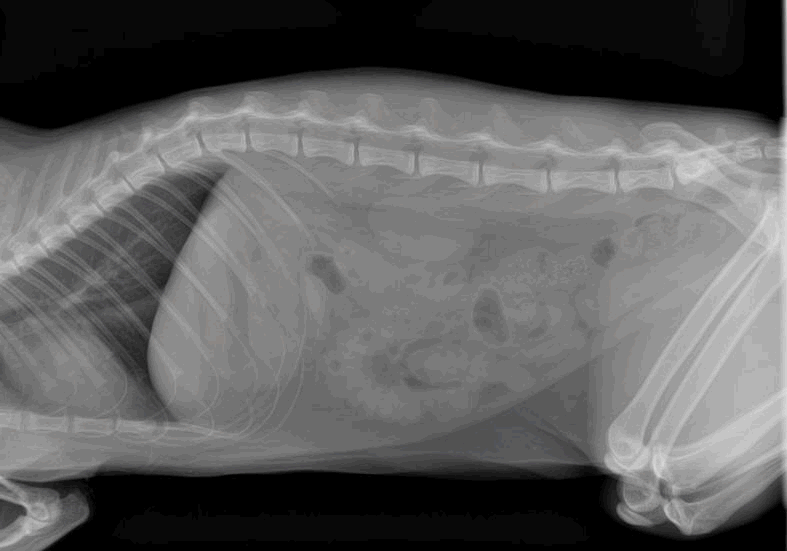

XRay image of obese cat with complete intestinal obstruction

XRay image of obese cat with complete intestinal obstruction Normal Cat Intestine X Ray The normal ultrasonographic dimensions of the more common abdominal nodes of the 10 healthy, adult, domestic shorthair cats investigated by schreurs et al are presented in table 1. The normal gi tract is addressed in an accompanying article in this issue of jfms. It is the round white area just above the white arrow. A ratio <1.28 is a strong. Normal Cat Intestine X Ray.